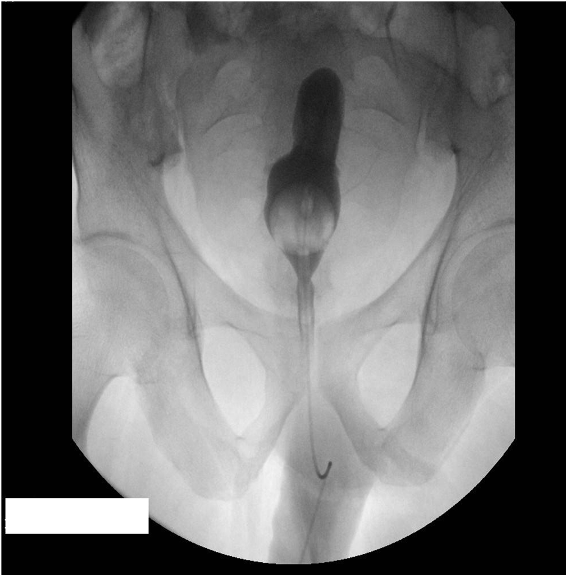

Pelvic Lipomatosis

Author(s)Sikander Ali Khan, MD